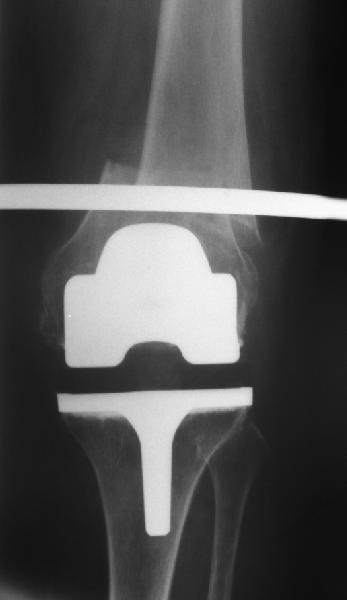

То, что планируется - наиболее распространенный подход. Еще менее инвазивный вариант - закрытый антеградный интрамедуллярный остесинтез. Мы используем гвозди, которые выпускаются предприятием ЦИТО, т.е. недорогие. Там в дистальное отверстие можно ввести 3 винта (2 снаружи и один навстречу), еще и угловая стабильность получается.

Александр Николаевич, сколько у вас таких клиентов? Каковы исходы? Только ли ЦИТОвские стержни использовали? Были ли с неправильно сросшимися переломами? У меня есть 2 клиента. Только переломы срослись у одного с вальгусом у другого с варусом. Планирую ту же схему через остеотомию.